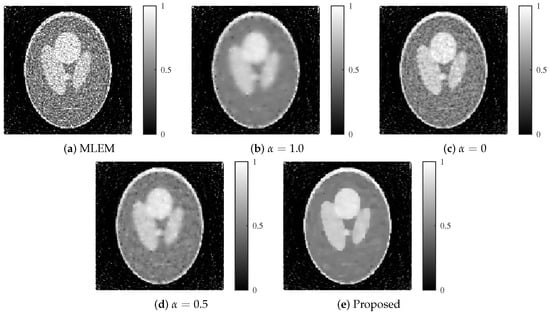

Reconstructed images for each method with an SNR of 30 dB. (a) MLEM, (b) MLEM with L1 regularization (), (c) MLEM with L2 regularization (), (d) MLEM with ElasticNet regularization ( fixed), and (e) proposed dynamic ElasticNet regularization. The proposed method exceled in both noise reduction and image detail preservation.

Figure 10.

Reconstructed images for each method with an SNR of 25 dB. (a) MLEM, (b) MLEM with L1 regularization (), (c) MLEM with L2 regularization (), (d) MLEM with ElasticNet regularization ( fixed), and (e) proposed dynamic ElasticNet regularization. The proposed method excels in both noise reduction and image detail preservation, even under high noise conditions.

Similar to the Shepp–Logan results, the MLEM method diverged as the number of iterations increased at SNR levels of both 30 and 25 dB. For the fixed ElasticNet method with , intermediate performance was observed between and at 30 dB. However, at 25 dB, the case resulted in a lower evaluation function value than that for . In contrast, the proposed method consistently exhibited stable performance across all noise levels and maintained low evaluation function values, even under the high-noise condition of 25 dB.

The reconstructed images produced by each method are shown in Figure 9 and Figure 10. The proposed method achieved an optimal balance between noise and resolution compared with the other methods, even at noise levels of 30 and 25 dB.